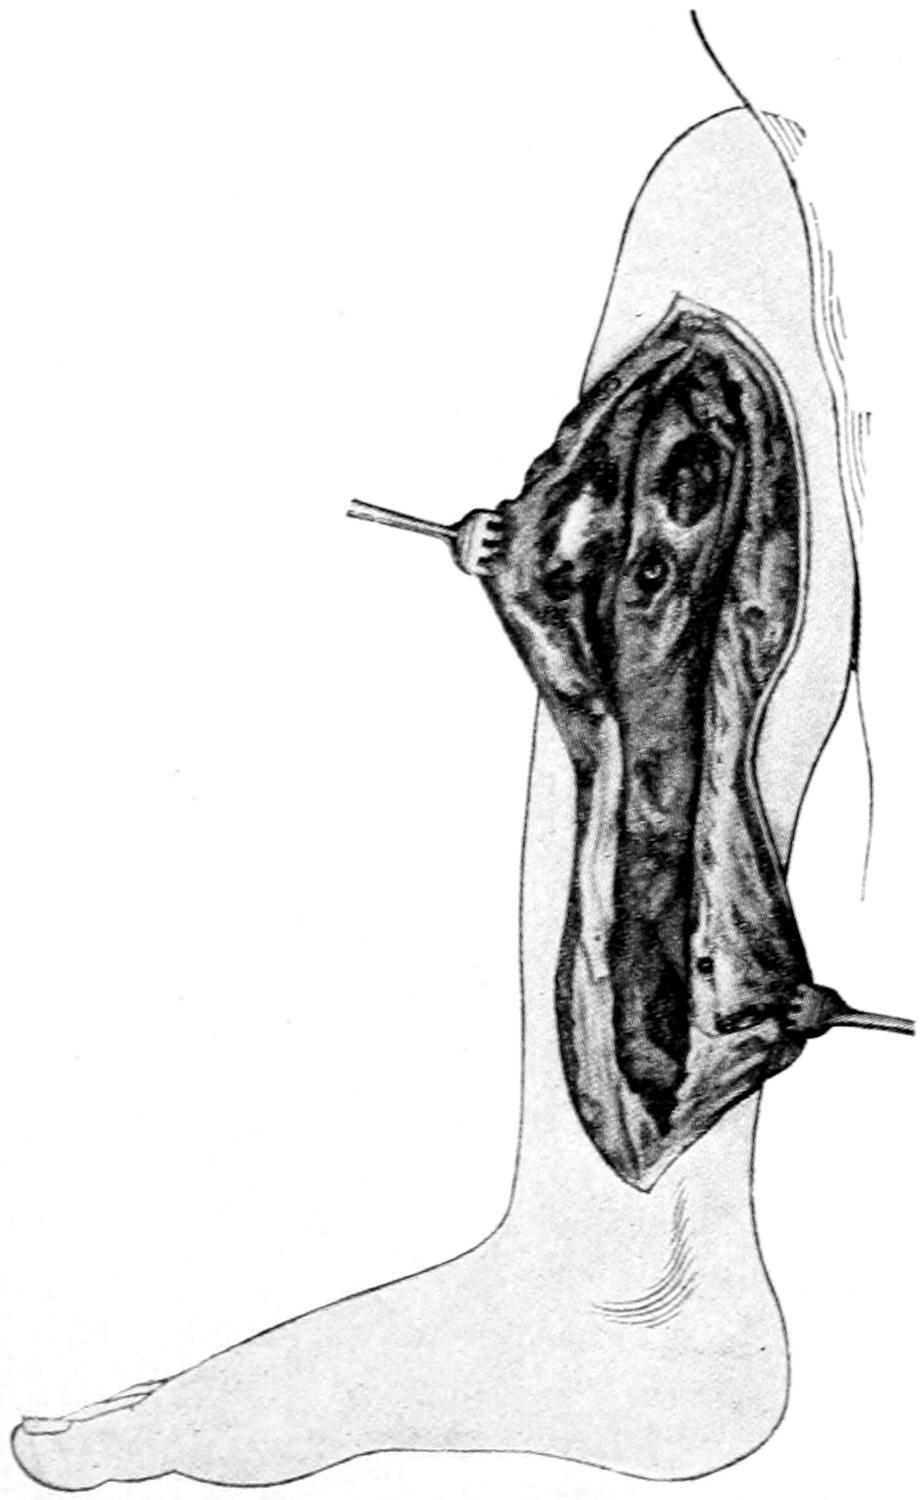

Fig. 1

Congenital hypertrophy: gigantism of both lower extremities. (Case of Dr. Graefe [Sandusky].)